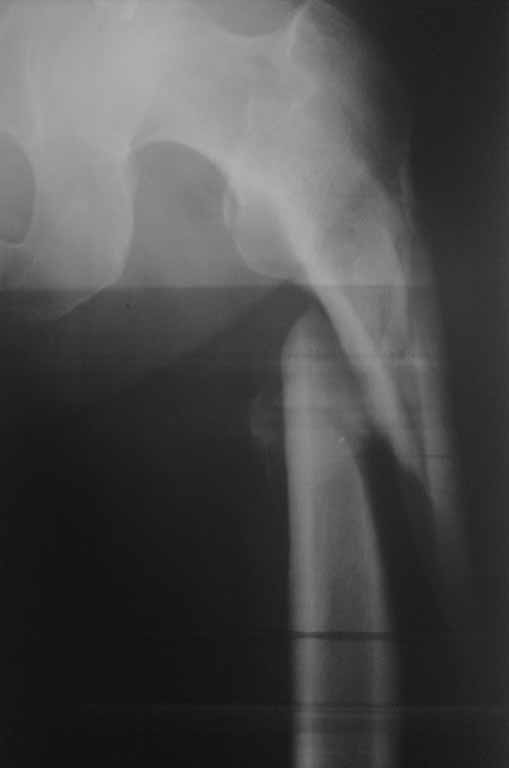

Судя по р-грамме, по имеющимуся "облачку" на медиальной стороне, идет консолидция отломков.

Так что - только открытое, одномоментное выправление. Осторожненько поработайте распатором, освобождая от мозоли (лучше используйте круглый распатор Кобба!) и медленно растягивайте на дистракционном ортопедическом столе, под контролем ЭОП-а.

PFN 340mm отнюдь не короткий, я бы даже сказал длинноват, для Вас он метод выбора! Готовьтесь к большой кровопотере! 1,5литра не исключено. Есть ли у Вас CellSaver?

K сожалению, Вы не указали на сторону перелома голени. Если со стороны перелома бедра, то это ухудшит ситуатцию для дистракции... Также нет снимков голени